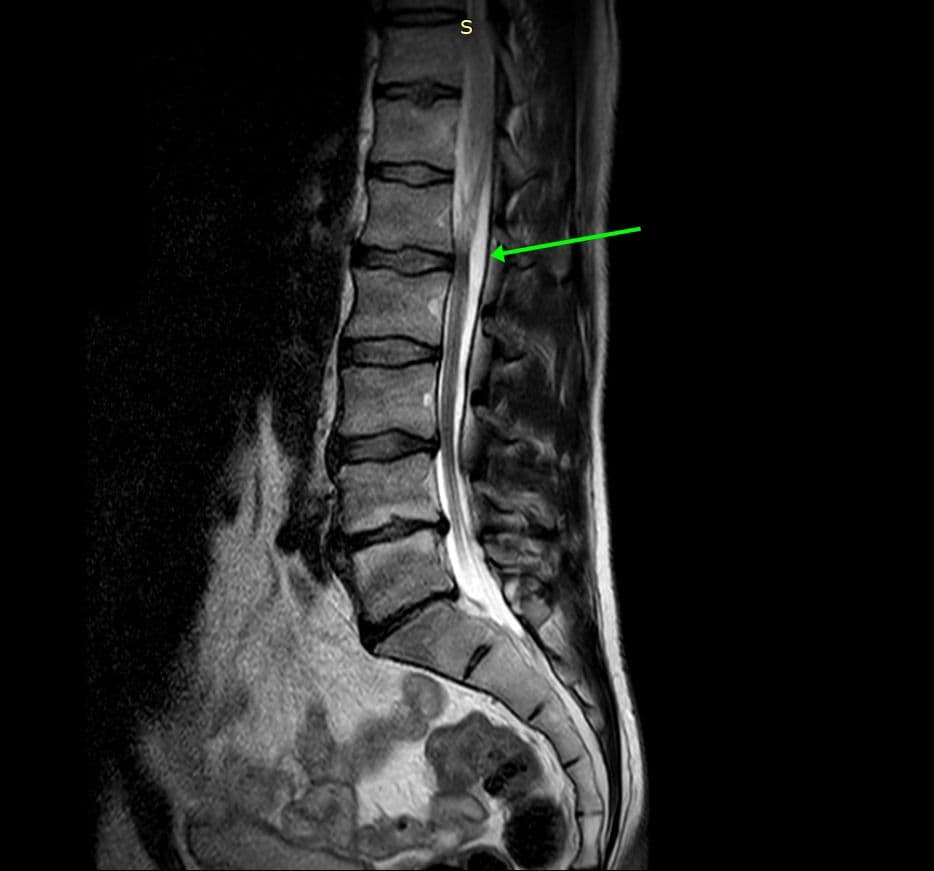

Attente osseuse axiale de la sclérose tubéreuse de Bourneville, ou complexe de sclérose tubéreuse (TSC).

Tumeur bénigne relativement rare de découverte fortuite sur un bilan de lombalgie.

MRI